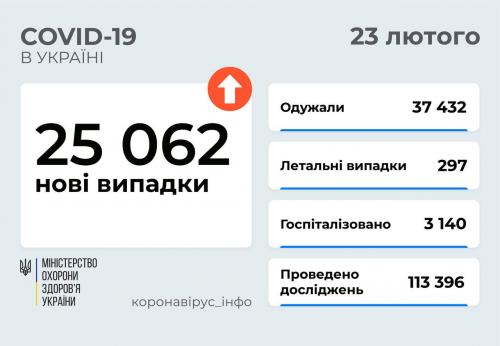

МОЗ: Уперше з початку пандемії було зроблено понад 100 тисяч ПЛР-досліджень за добу